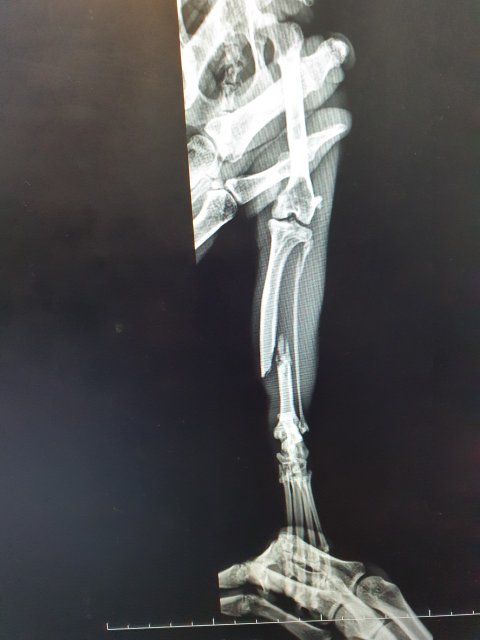

- 왼쪽 뒷다리 탈구, 관절염

그런데 송이가 내려오는 착지 과정에서 잘못됐는지 몇시간이 지나서 아팠던 다리가 부러진 듯 아예 못쓰는 상황이었고 오늘 캣맘분이 병원에 데려가셨는데 심하게 골절되어 당장 수술하지 못하면 다리를 절단해야하는 상황이에요.